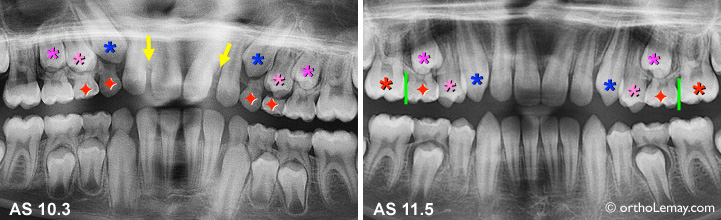

Extractions sélectives ayant permis d’améliorer la direction d’éruption des canines (*bleu) et premières prémolaires (*rose pâle) en 14 mois. Ces dents se sont redressées et on diminué les espaces entre les incisives (flèche jaunes) en faisant éruption. L’étape suivante à 11.5 ans serait d’extraire les secondes molaires temporaires (rouge) et de poser un mainteneur d’espace pour éviter la migration vers l’avant des premières molaires permanentes (*rouge).